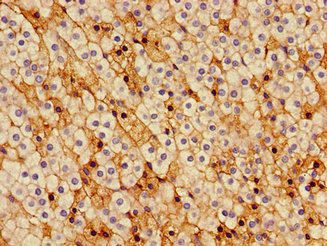

Immunohistochemistry of paraffin-embedded human adrenal gland tissue using CSB-PA004822LA01HU at dilution of 1:100